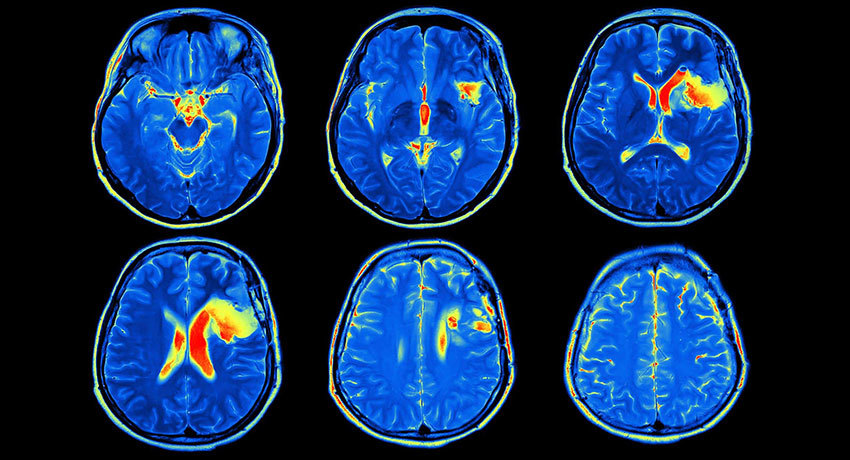

Магнитно-резонансная томография с контрастом хорошо выявляет опухоли. На снимках видны даже очень небольшие образования.

Магнитно-резонансную томографию с контрастным усилением нередко применяют для диагностики злокачественных опухолей, некоторых инфекций, патологий кровеносных сосудов, нервной системы. Это эффективный метод оценки активности и типа течения рассеянного склероза, поиска отдаленных метастазов при злокачественных опухолях.

Патологии головного мозга:

метастазы рака, инфекции, нарушения со стороны гипофиза, рассеянный склероз, нейрофиброматоз.